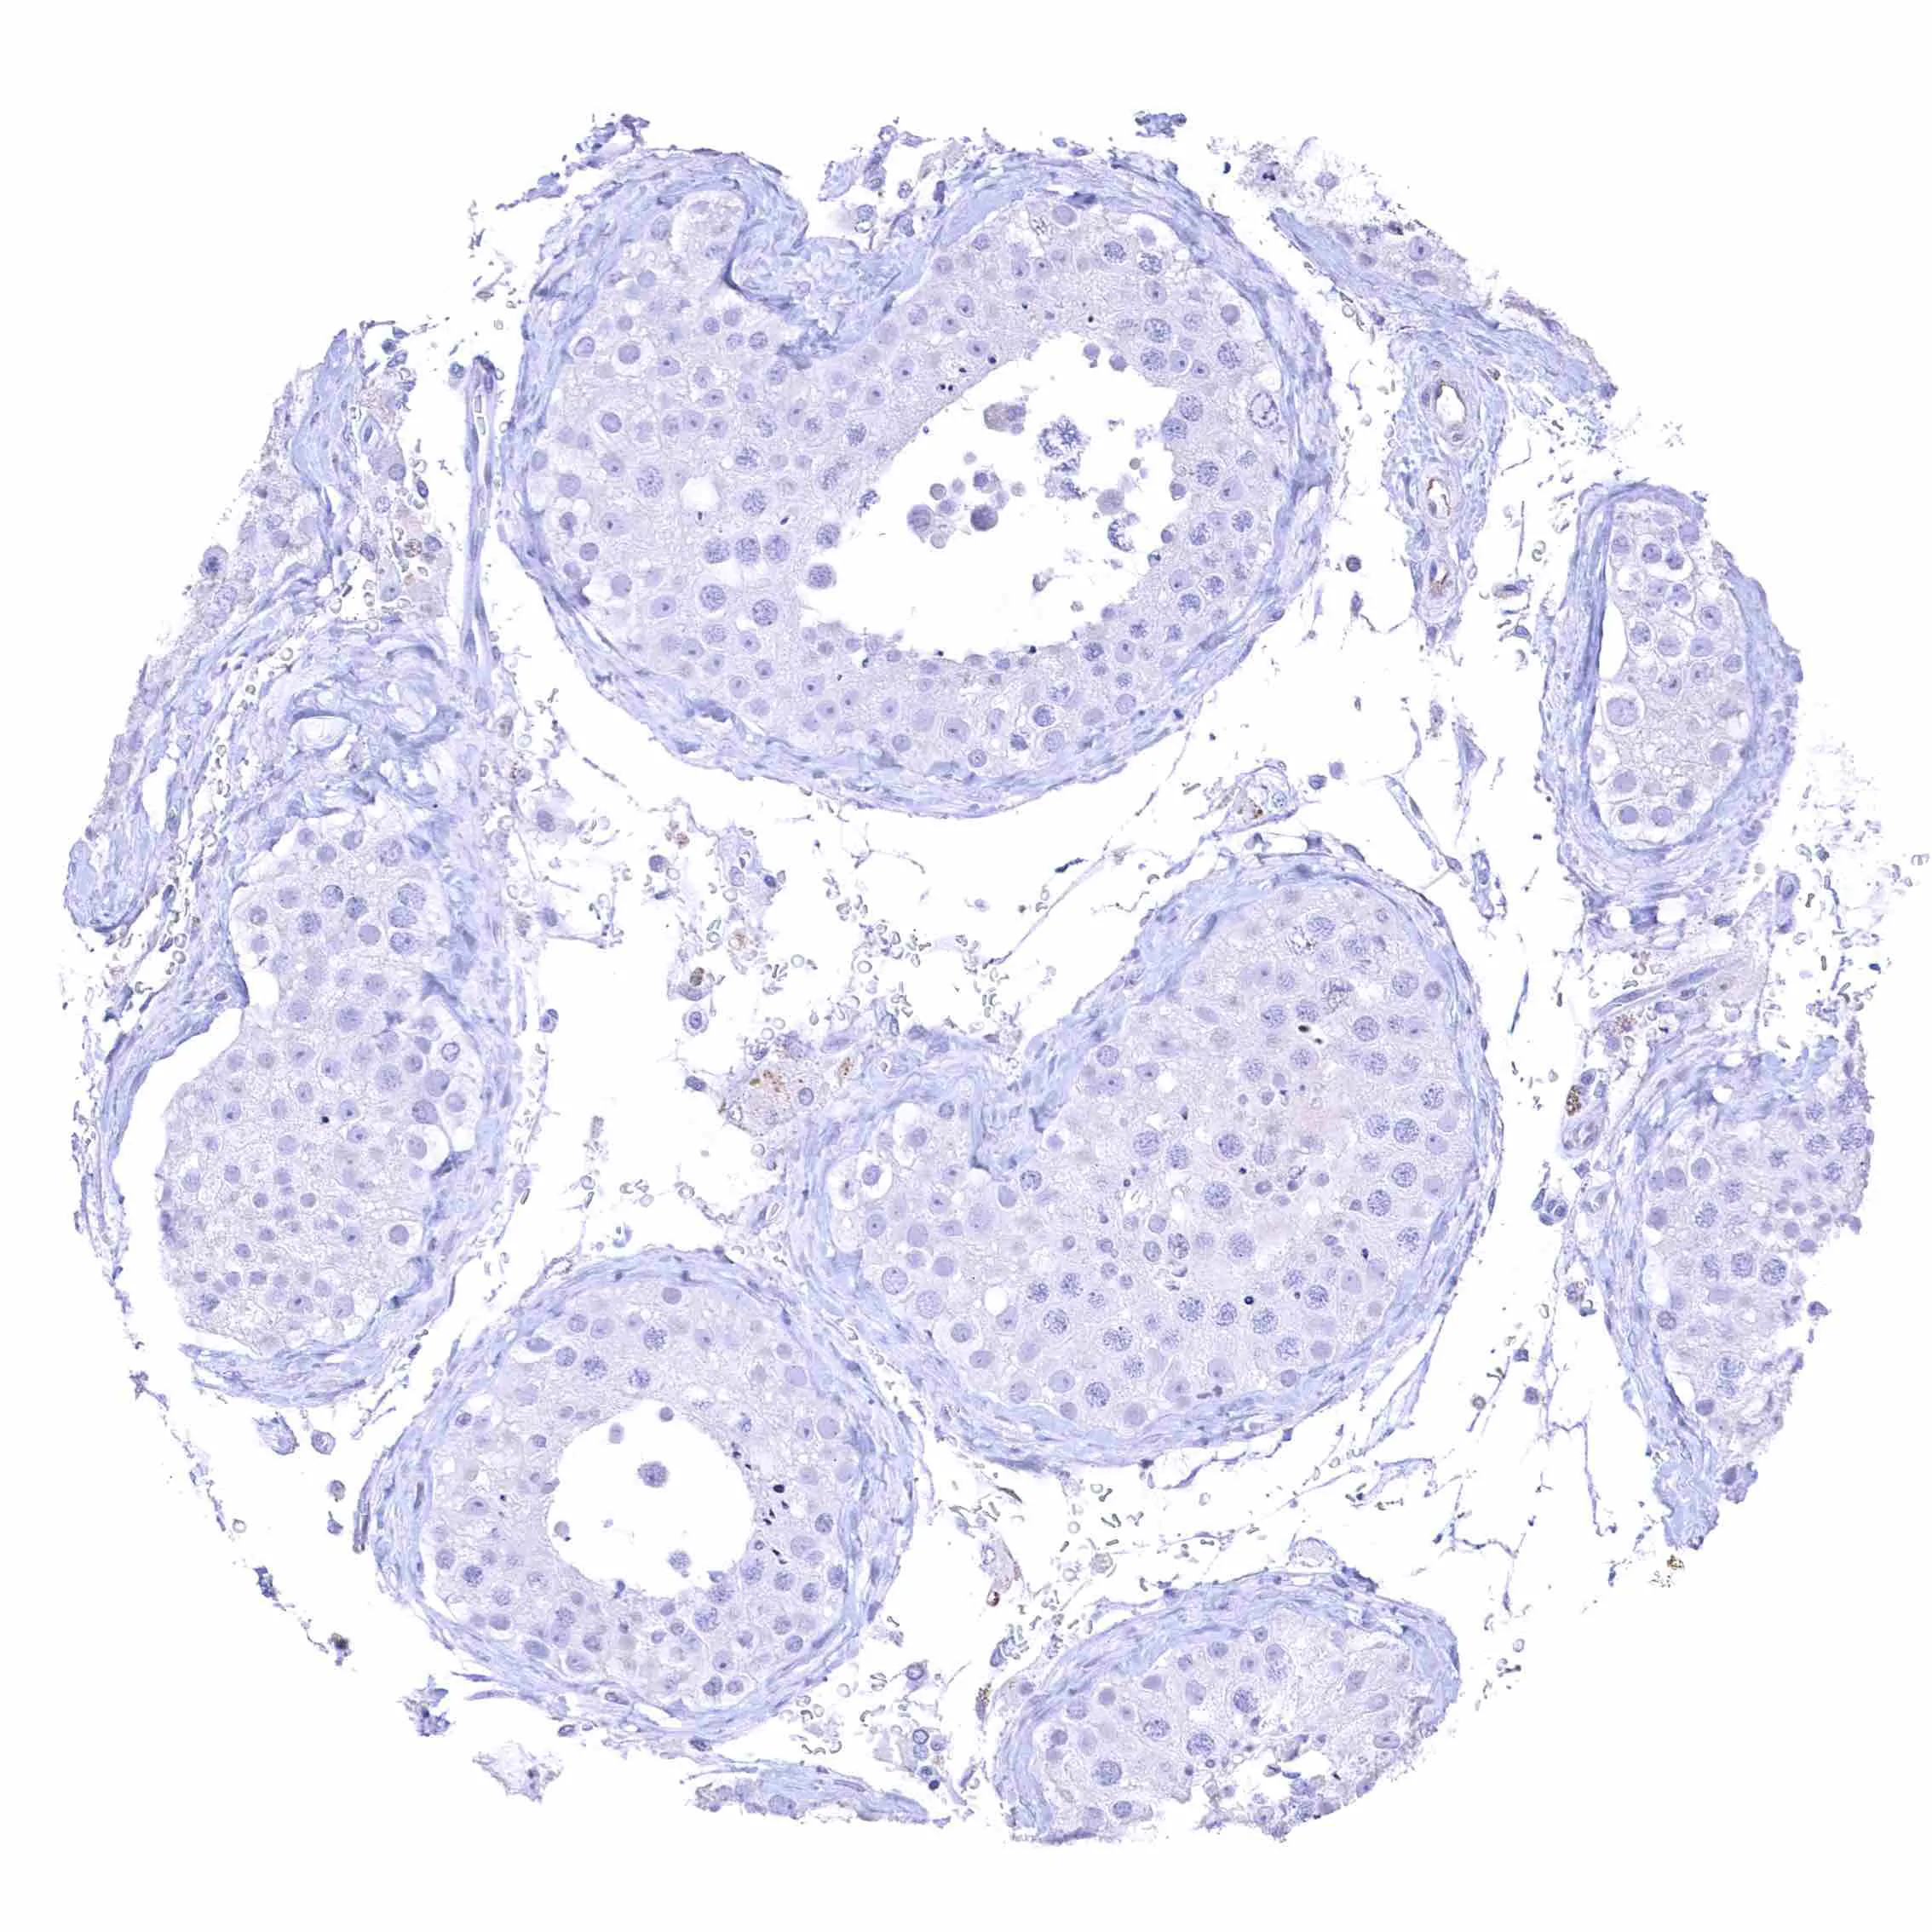

Testis